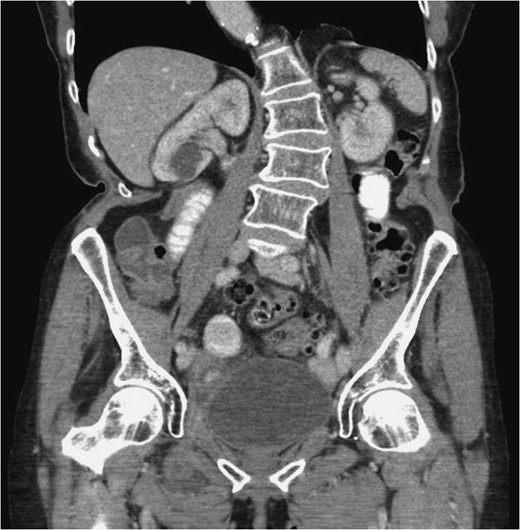

Coronal plane. The right obturator hernia is demonstrated. It contains small bowel loop. Proximal small bowel is mildly dilated. Right obturator hernia with features of incomplete small bowel obstruction.